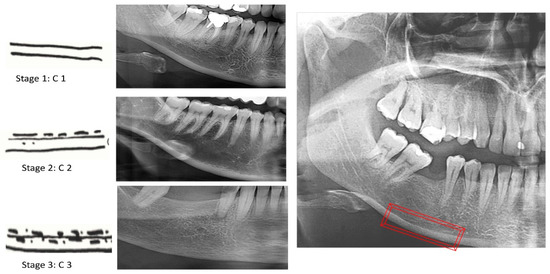

Furthermore, the MCI index is a three-stage qualitative evaluation of the mandible’s lower border porosity that is connected to bone mineral density and which has already been confirmed to be a suitable technique for osteoporosis screening [2,3,10,11,12,13,14,15,16,17]. MCI is applied bilaterally on panoramic radiographs at the lower border of the mandible posterior to the mental foramen and is classified subjectively into three stages. In stage 1, the cortical endosteal margin looks even and consistent. When the endosteal margin presents signs of semilunar deficiencies or one to three layers of cortical endosteal remain, it is categorized as stage 2. The cortical layer reaches stage 3 when it has numerous (>3) endosteal semilunar deficiencies and is obviously porous. The higher category (stage 3) indicates a significantly higher likelihood of osteoporosis compared to the lower (stage 2). Since MCI usually presents good sensitivity but low specificity, which can result in increased false positive results and needless DXA examinations, it is preferable to be used in combination with other indexes or clinical risk assessment tools [2,3,4,5,6,7,11].

MCI is a three-stage index, as shown in Figure 2:

C1: the endosteal edge of the cortex is even and precise on both sides.

C2: the endosteal edge exhibits semilunar deficiencies (lacunar resorption) or appears to have endosteal cortical fragments (1–3 layers), solely on a single side or on both sides.

C3: the cortex is obviously porous and has intense endosteal cortical residue fragments.

Figure 2. Classification of the MCI index (The area of evaluation in red).